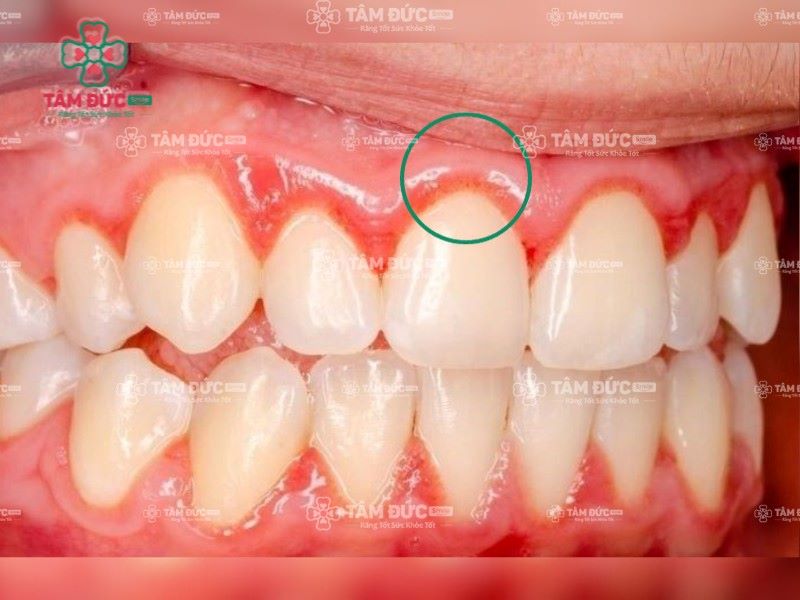

Cao răng là một trong những nguyên nhân gây viêm lợi chân răng